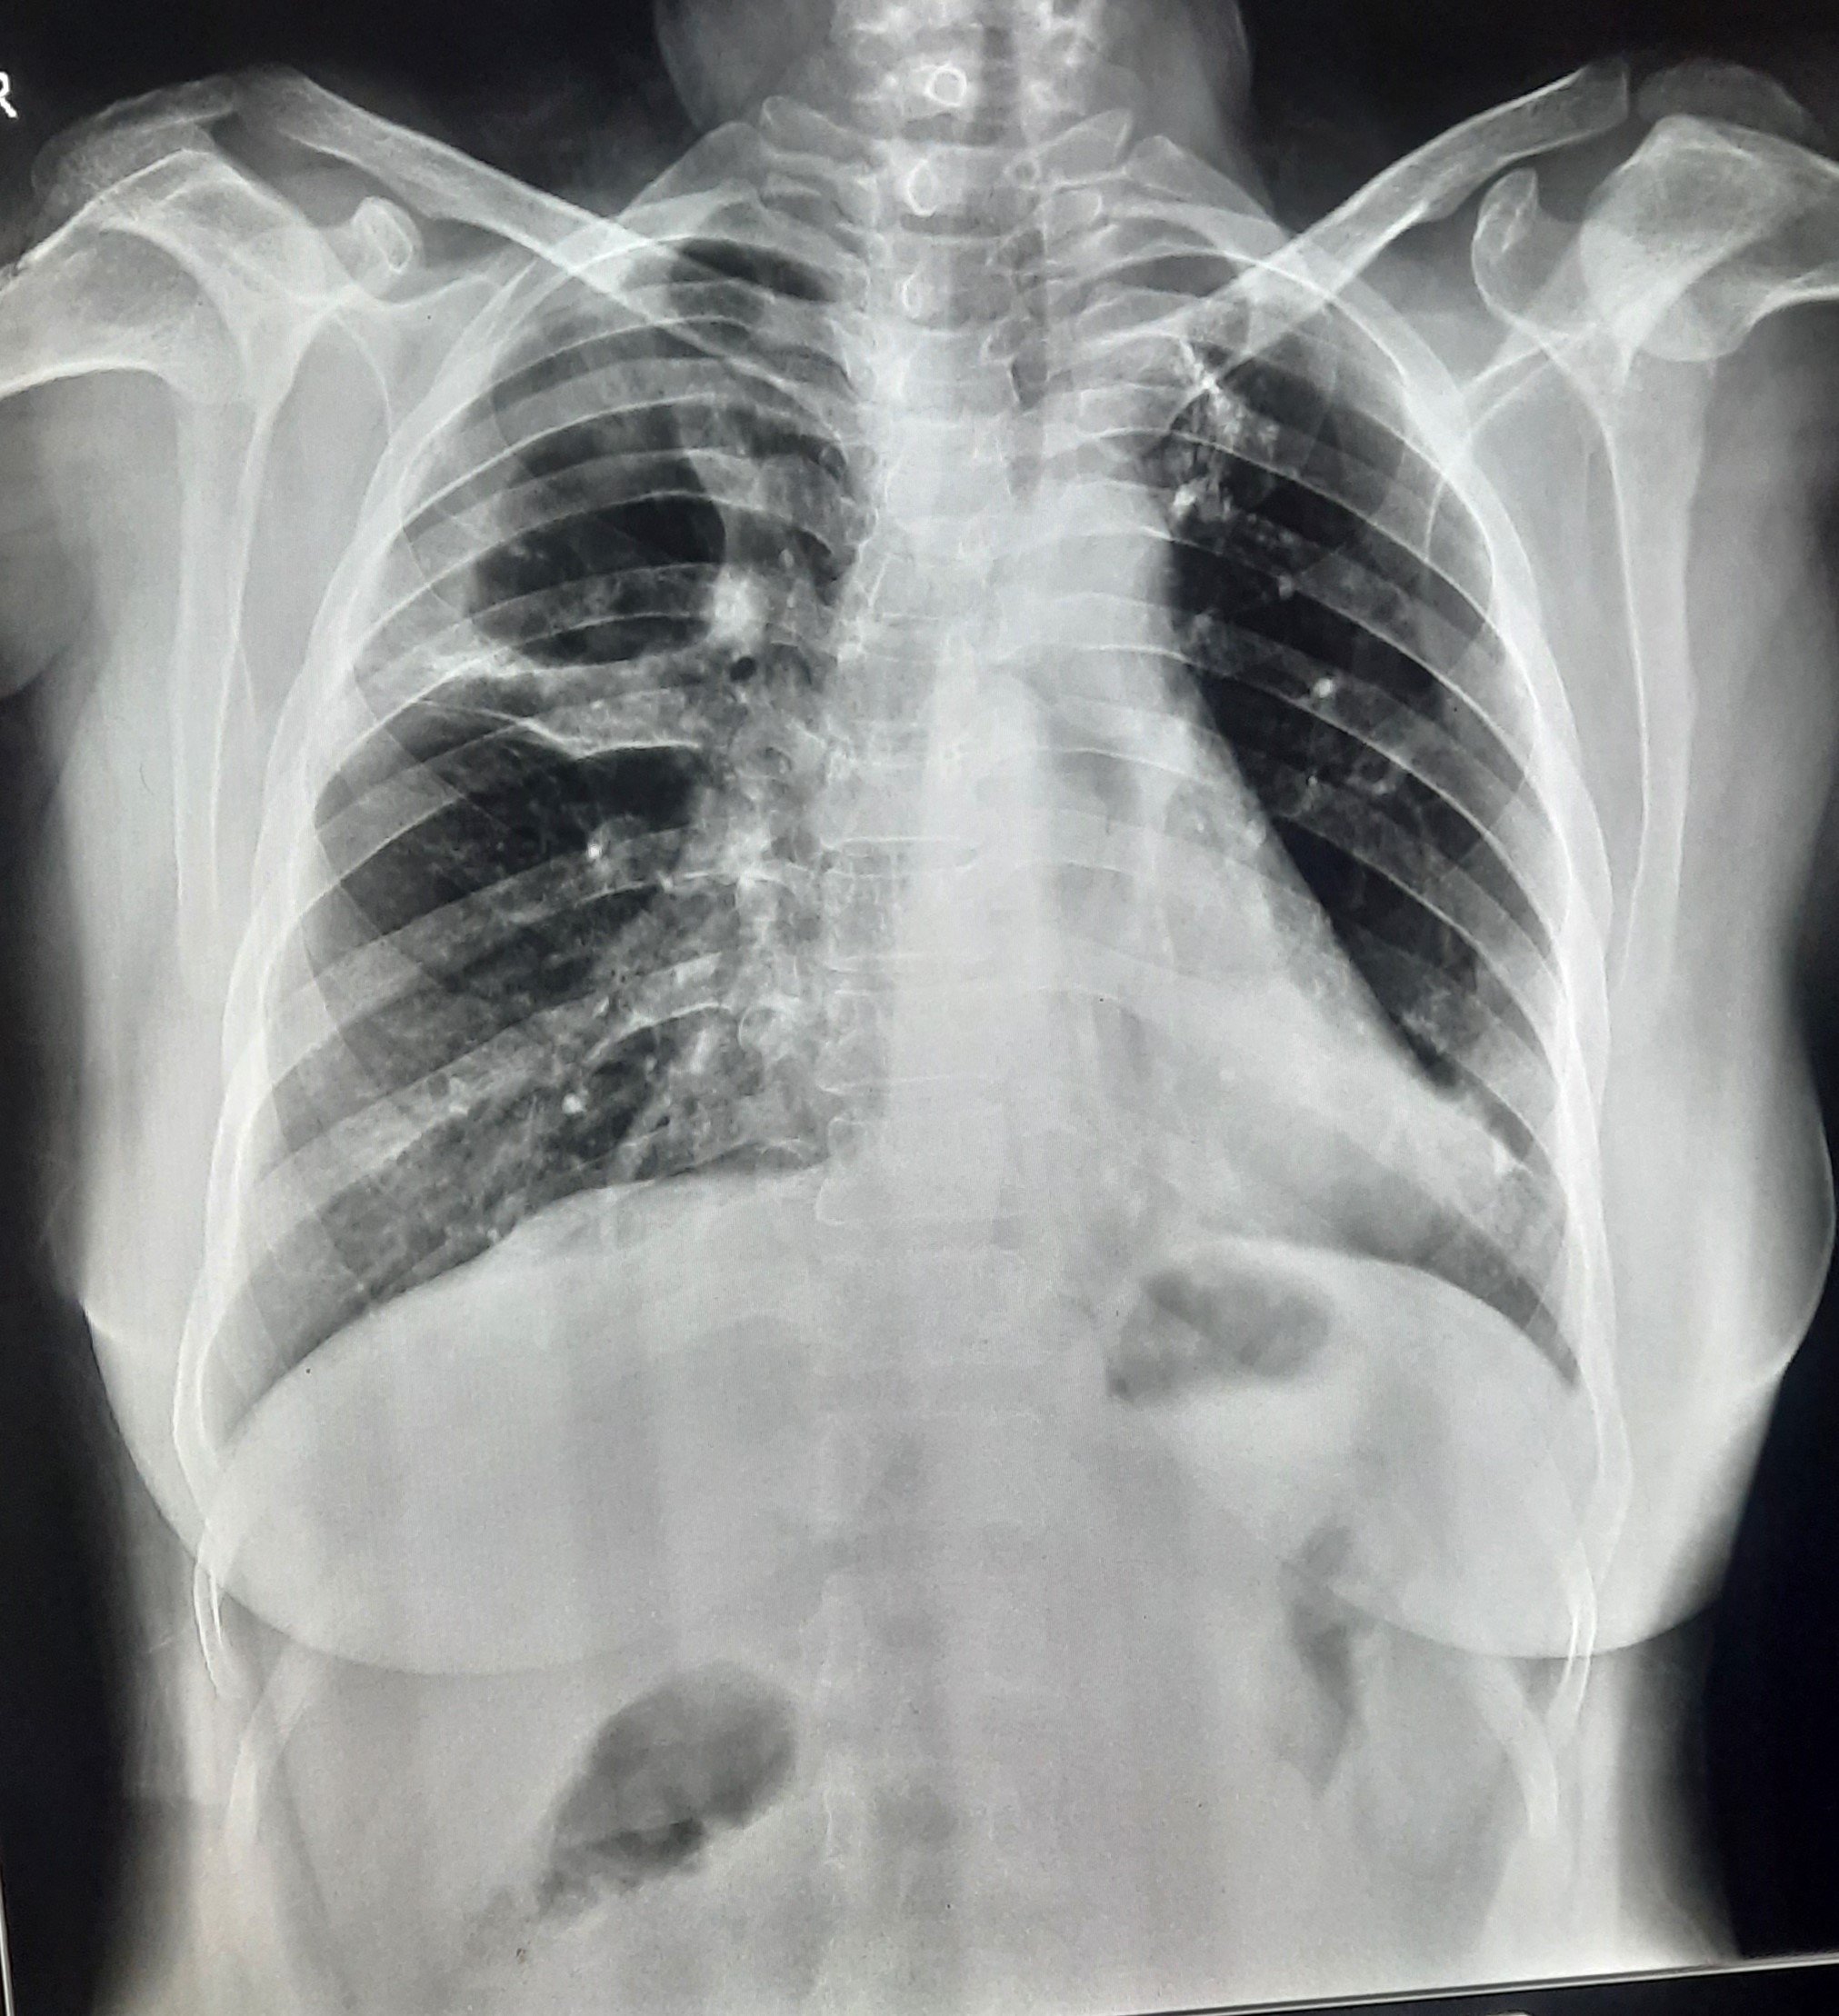

| 123 | IGGMC, Nagpur, Nagpur | P2 | 29-4349 | Dhammadip Wasnik | Consent taken on Paper | 35 Yrs. |

Provisional Diag : PTB Follow-up

Final Diag : Pulmonary Tuberculosis (Microbiologically Confirmed PTB) |

TB Case (Confirmed) | Abnormality visible on x-ray |